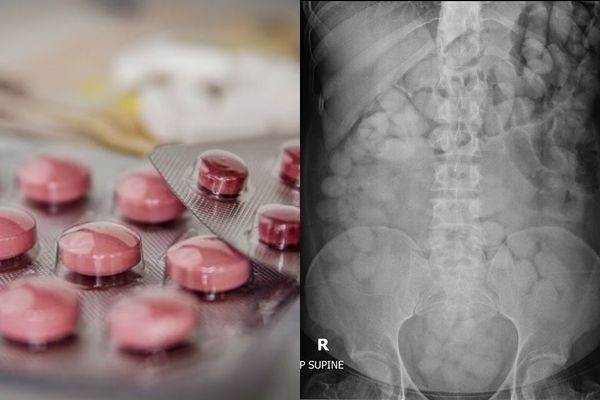

南韓一名男子日前鋌而走險做起人體運毒的生意,他先是吞入上百包用塑膠袋包裹的搖頭

丸以及1包K他命,隨後從泰國搭機返國。然而他雖躲過海關,但僅僅1天後就被人發現陳

屍家中,死因為搖頭丸急性中毒,當時他血液中的搖頭丸濃度高達每公升20.36毫克。法

醫相驗後,竟在他的胃部發現79袋包裝破裂的搖頭丸。

▲人體運毒者體內全是一袋袋的毒品。(圖/ : The Customs

Department)

死者的遺體經過法醫相驗後,果然在胃部發現上百袋單顆包裝的搖頭丸,其中有79袋的包

裝已經破裂,另外則有約130袋是完好無損的。警方判斷,死者應該是受人委託進行人體

運毒,然而過程中因為包裝袋破裂,導致大量的搖頭丸瞬間被吸收,因而暴斃。據悉,一

旦體內裝有毒品的袋子破裂,很有可能會導致死亡,因此人體運毒者不但不可以劇烈運動

,還要避免進食。

除此之外,法醫還在他的腸道發現118公克的K他命,足以讓600多人同時服用。經警方調

查,該名男子8月才剛從泰國出境,沿途經過馬來西亞,並在9月24日抵達南韓,怎知25日

就暴斃,而當初向警方通報死亡的同居人目前也被列入調查。